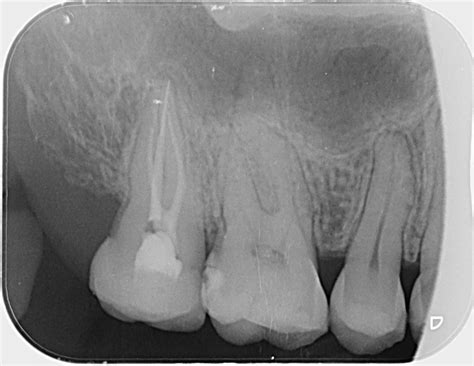

When you visit your dentist for a toothache or a routine check-up, they may recommend a specific type of dental imaging to get a clearer picture of your oral health. Among the various diagnostic tools available in modern dentistry, the Periapical X Ray stands out as an essential imaging technique. Unlike broader panoramic X-rays that capture the entire jaw, a periapical image focuses on one or two specific teeth, providing an incredibly detailed view of the tooth from the crown down to the very tip of the root and the surrounding bone structure. Understanding what this procedure entails can help alleviate any anxiety you might feel about your upcoming dental appointment.

A Periapical X Ray, often referred to simply as a "PA," is a close-up, high-resolution diagnostic image. The term "periapical" literally translates to "around the apex," with the apex being the tip of the tooth root. This specific type of X-ray is designed to show the entirety of the tooth—from the biting surface (crown) down to the root end—as well as the surrounding supporting bone.

Because it offers such fine detail, dentists utilize this scan to diagnose specific problems that might be missed by broader imaging methods. Whether you are experiencing localized pain, sensitivity, or require a procedure that demands precision, this X-ray is often the first step toward an accurate diagnosis.

The primary purpose of a Periapical X Ray is to identify issues that are hidden from the naked eye. While a dentist can see the surface of your teeth, they cannot see the bone, the roots, or the hidden areas of decay between teeth without imaging. Here are the most common reasons why your dentist might order this scan:

• Detecting Abscesses: To see infections or pockets of pus forming at the tip of the root.

• Root Canal Planning: To visualize the shape, length, and condition of the root canals before performing a root canal treatment.

• Identifying Bone Loss: To evaluate the health of the bone supporting the teeth, which is crucial for diagnosing periodontal disease.

• Diagnosing Impacted Teeth: To determine the exact position of wisdom teeth or other teeth that haven't fully erupted.

• Trauma Assessment: To check for fractures or damage to the root after an injury to the mouth or jaw.